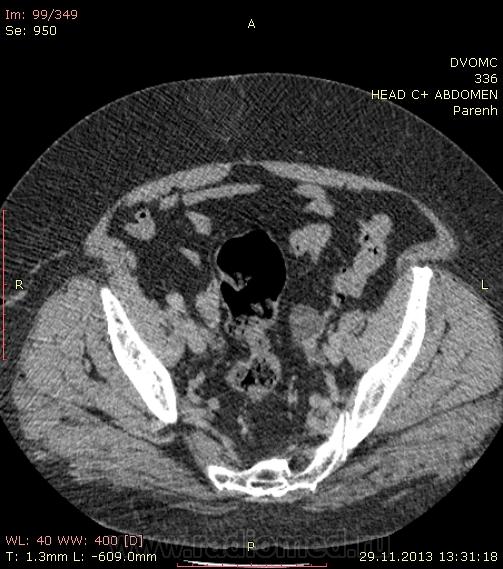

Пациентка 66 лет. В 2010 году мастэктомия слева - Cr II B ст., псориаз. Я нашел: образование нижнего полюса правой почки, образование в антральном отделе желудка по малой кривизне, киста яичника слева...в желчном пузыре много газосодержащих камней(?), лимфоузлов вроде не видно. Всё, кроме образования желудка находили ранее на УЗИ да на МРТ. Коллеги, посмотрите, можт я чё пропустил или неправильно понял. Какие мысли по поводу образований - особенно желудка(GIST? mts?)  DICOM здесь http://files.mail.ru/2C4F7CA79A884D37B3C86FF69C3D8D67

Мне кажется, что маловато контраста на вес пациентки. Почечно-клеточная (как более вероятная) карцинома правой почки, в стенке желудка написала бы мтс. Газосодержащие камни желчного пузыря. Кистовидное образование яичника. Киста печени, кисты почек. Дивертикулез толстой кишки. А что с жиром в грыже (вроде пупочная))) - наверное, последствие инфаркта сальника.